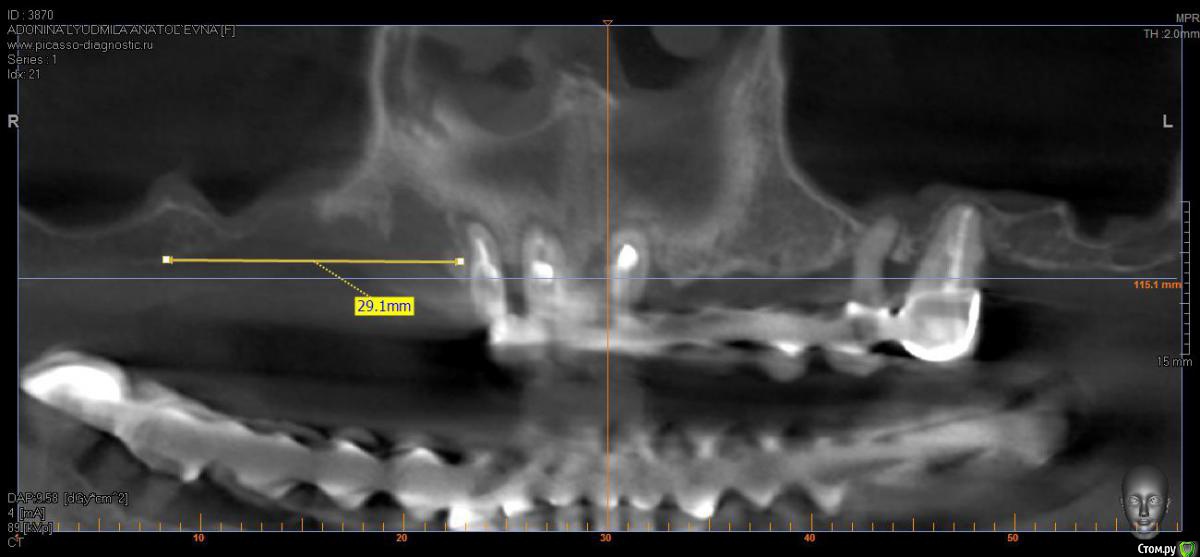

борисович Опубликовано 16 февраля, 2017 Поделиться Опубликовано 16 февраля, 2017 Уважаемые коллеги какой метод реконструкции возможен в данном клиническом случае. Пациент хочет только не съемное, и вариант временной конструкции на время реабилитации после костных реконструкций. Ссылка на комментарий

dok1 Опубликовано 16 февраля, 2017 Поделиться Опубликовано 16 февраля, 2017 Да мало ли что хочет. А если нельзя? Нет возможности? Какие варианты? У вас есть возможность сделать синус и имплантацию одновременно. Рисково, но может получиться. Но на операционные места я б побоялся что-то сверху класть. Ссылка на комментарий

борисович Опубликовано 16 февраля, 2017 Автор Поделиться Опубликовано 16 февраля, 2017 Если сделать только синус получиться поставить импланты только в проекции 16,17 . В проекции 14,15 строение гайморовой пазухи узкое очень, вы думаете не стоит заниматься вертикалью? Спасибо за ответ Ссылка на комментарий

kladoffka Опубликовано 17 февраля, 2017 Поделиться Опубликовано 17 февраля, 2017 Вариант 4х зигом и тотал, имхо Ссылка на комментарий